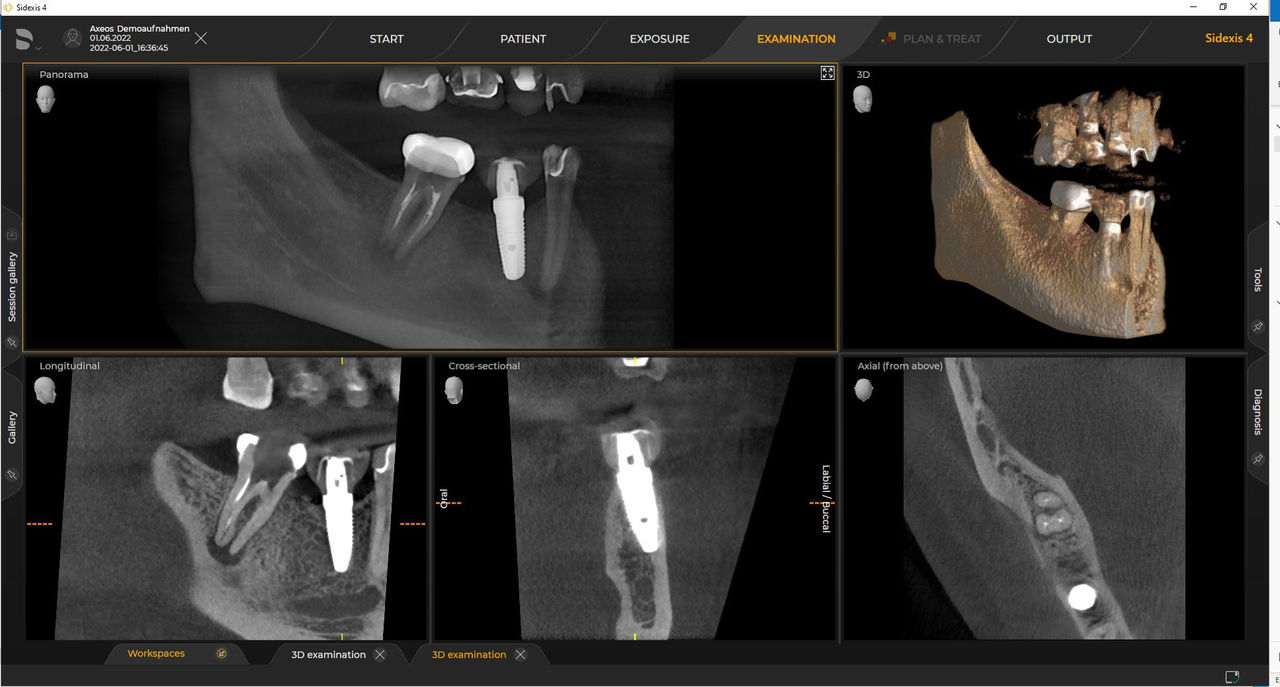

Las unidades 3D de Dentsply Sirona funcionan exclusivamente con Sidexis 4. Sin embargo, la migración de datos de Sidexis XG a Sidexis 4 es muy fácil. Sidexis 4 permite una experiencia digital completa con las últimas herramientas.

Con el modo de dosis baja inteligente, obtiene radiografías 3D en el rango de dosis de una 2D. En el modo HD (hasta 1400), las imágenes individuales se obtienen durante una única rotación y se convierten en un volumen 3D con hasta 80 μm para imágenes de bajo ruido en alta resolución